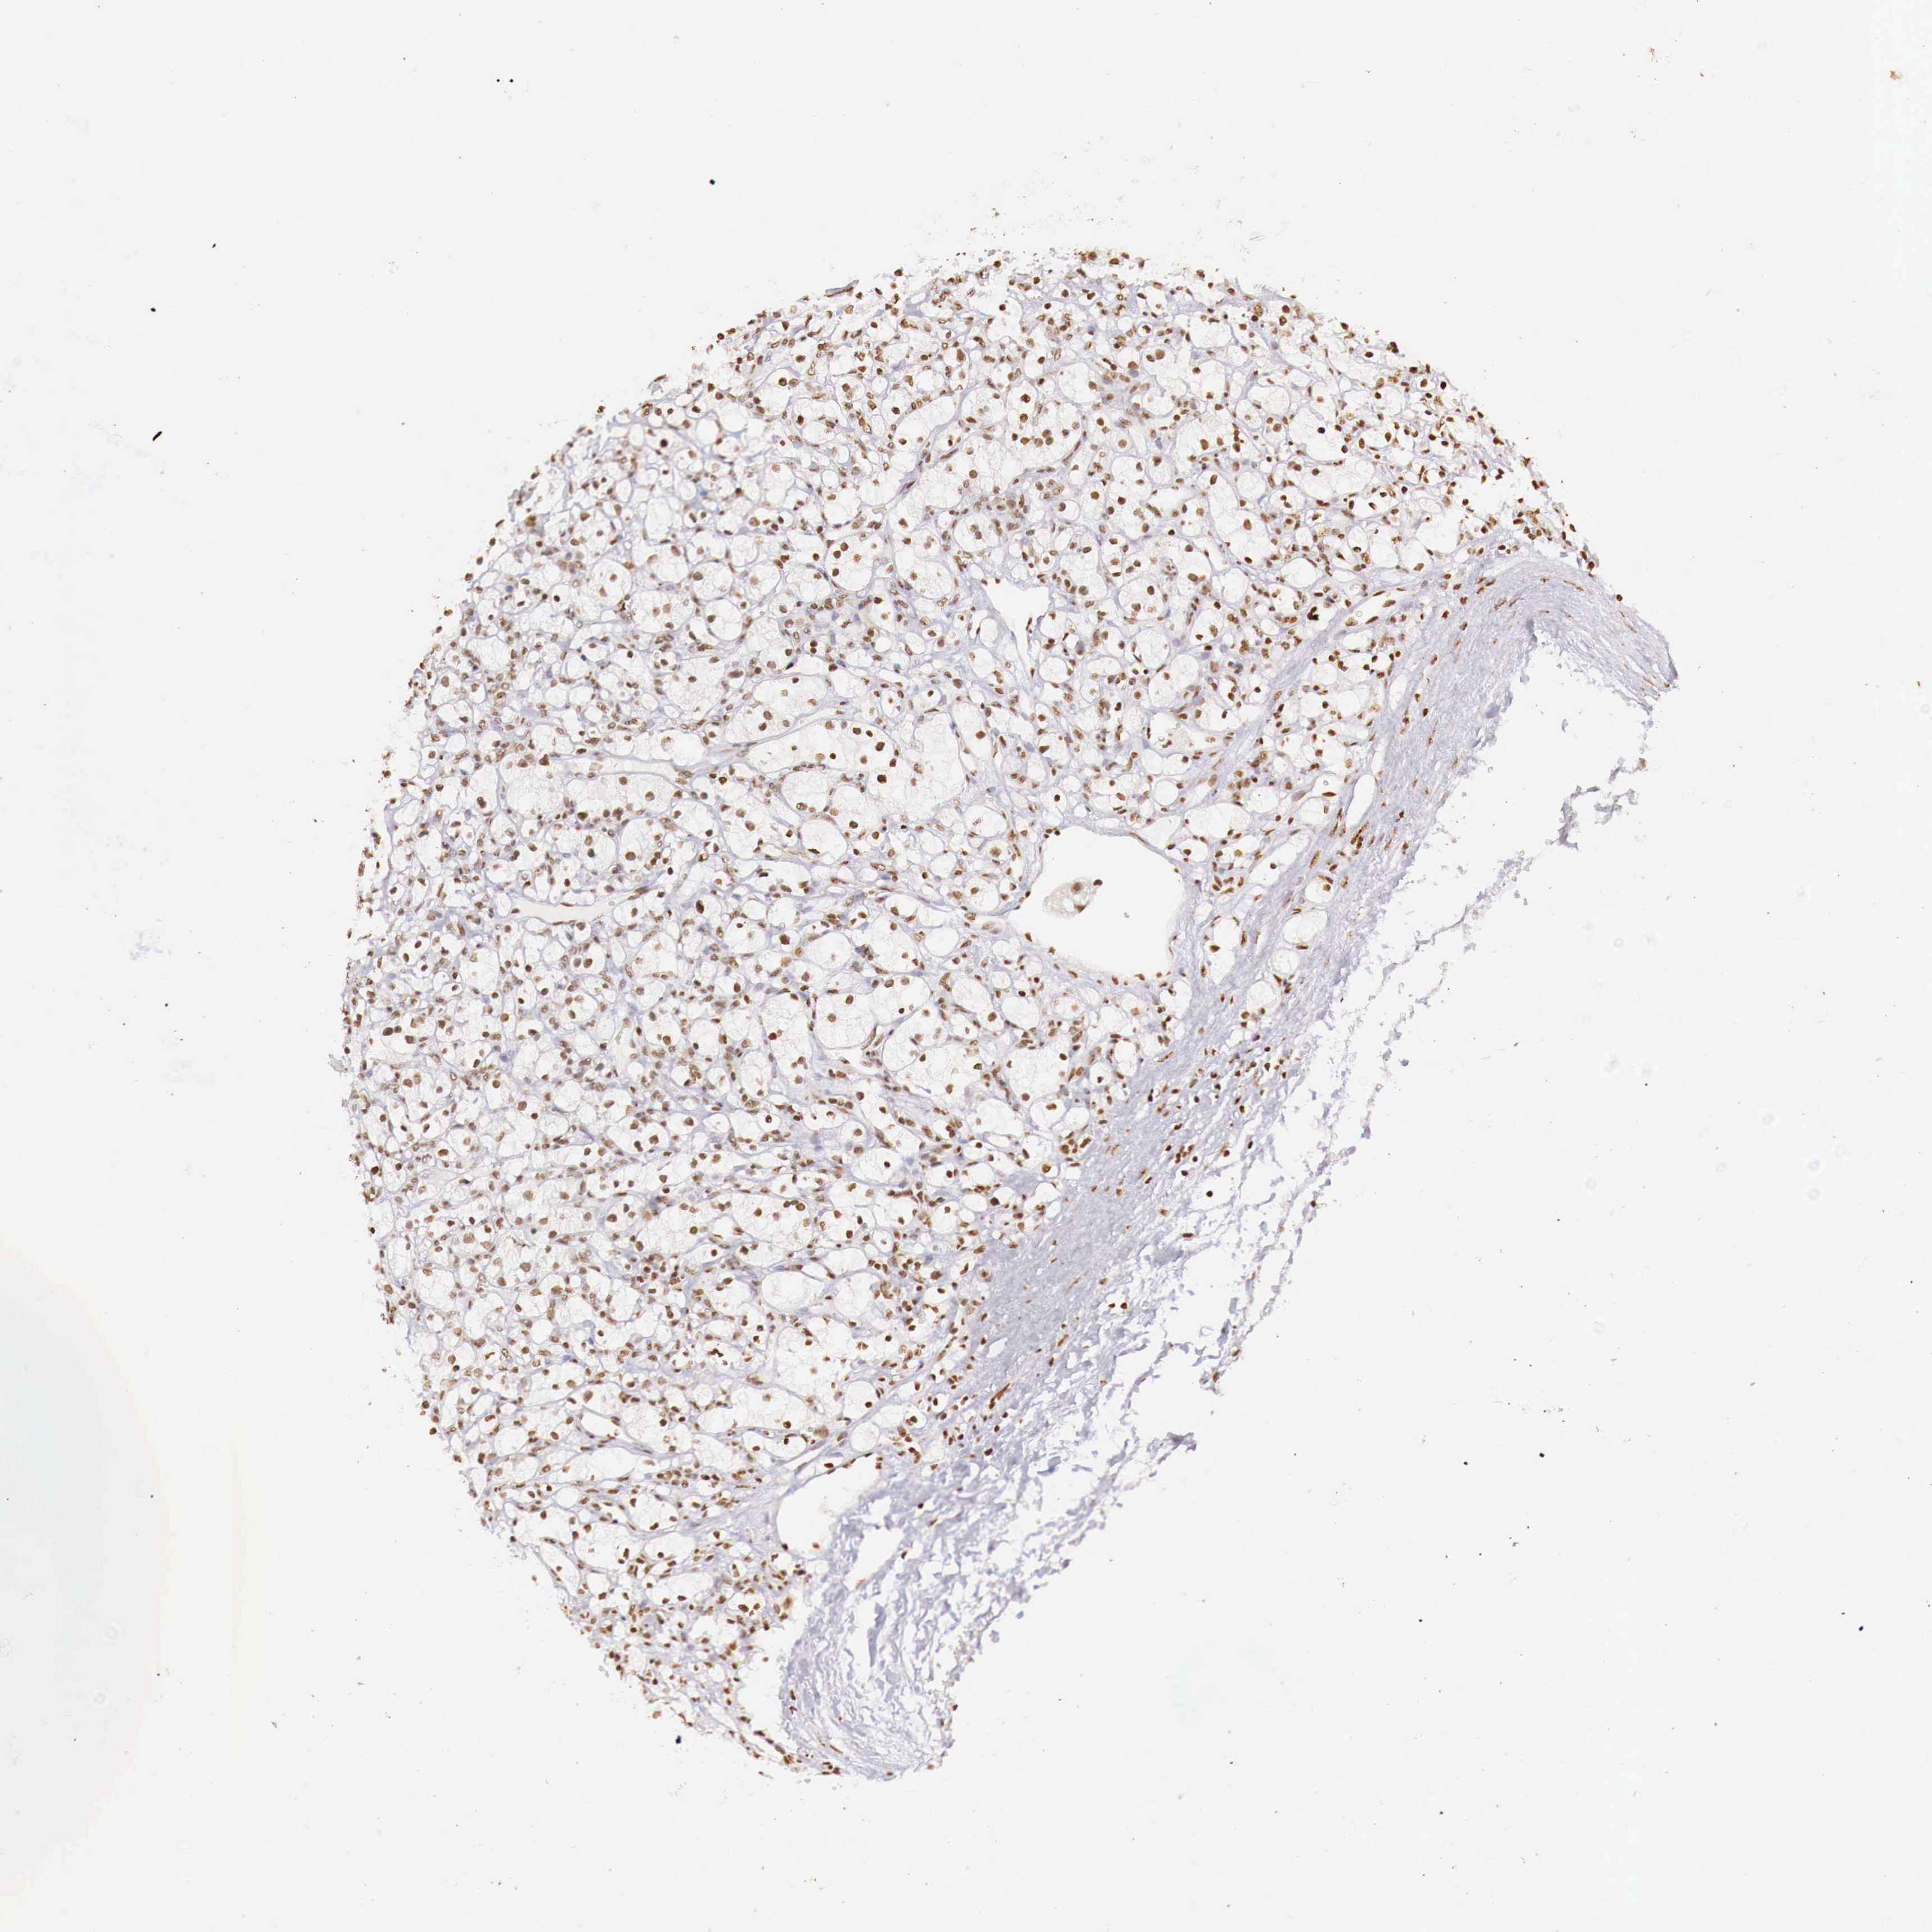

KIDNEY RENAL CLEAR CELL CARCINOMA (VALIDATION) - Interactive survival scatter ploti

The Survival Scatter plot shows the clinical status (i.e. dead or alive) for all individuals in the patient cohort, based on the same data that underlies the corresponding Kaplan-Meier plots. Patients that are alive at last time for follow-up are shown in blue and patients who have died during the study are shown in red.

The x-axis shows the expression levels (FPKM) of the investigated gene in the tumor tissue at the time of diagnosis. The y-axis shows the follow-up time after diagnosis (years). Both axes are complimented with kernel density curves demonstrating the data density over the axes. The top density plot shows the expression levels (FPKM) distribution among dead (red) and alive patients (blue). The right density plot shows the data density of the survived years of dead patients with high and low expression levels respectively, stratified using the cutoff indicated by the vertical dashed line through the Survival Scatter plot. This cutoff is automatically defined based on the FPKM cutoff that minimizes the p-score. The cutoff can be changed by dragging the vertical line or by entering a cutoff value in the square labeled "Current cut-off".

Under the Survival Scatter plot the p-score landscape (black curve; left axis) is shown together with dead median separation (red curve; right axis). Dead median separation is the difference in median mRNA expression between patients who have died with high and low expression, respectively. It is calculated as follows: median FPKM expression of dead patients with high expression - median FPKM expression of dead patients with low expression. This is intended to aid the user in visually exploring custom cutoffs and the associated p-scores and dead median separation.

Individual patient data is displayed and can be filtered by clicking on one or more of the category buttons on the top of the page. Categories describing expression level and patient information include: high, low, alive, dead, female, male and tumor stages. The scale of the x-axis can be toggled between linear and log-scale by clicking on the "x log" button. Mouse-over function shows TCGA ID, patient information and mRNA expression (FPKM) for each patient.

& Survival analysisi

Kaplan-Meier plots summarize results from analysis of correlation between mRNA expression level and patient survival. Patients were divided based on level of expression into one of the two groups "low" (under cut off) or "high" (over cut off). X-axis shows time for survival (years) and y-axis shows the probability of survival, where 1.0 corresponds to 100 percent.

DKC1 is not prognostic in Kidney Renal Clear Cell Carcinoma (validation)

Best expression cut offi

Based on the FPKM value of each gene, patients were classified into two groups and association between prognosis (survival) and gene expression (FPKM) was examined. The best expression cut-off refers the FPKM value that yields maximal difference with regard to survival between the two groups at the lowest log-rank P-value. Best expression cut-off was selected based on survival analysis .

When clicking on this number, the vertical dashed line indicating cut-off, the interactive survival plot, and the Kaplan-Meier curve will be adjusted to show results based on the best expression cut-off.

: 32.21

TCGA RNA samplesi

RNA-seq data is reported as average FPKM (number Fragments Per Kilobase of exon per Million reads), generated by the The Cancer Genome Atlas (TCGA) .

Normal distribution across the dataset is visualized with box plots, shown as median and 25th and 75th percentiles. Points are displayed as outliers if they are above or below 1.5 times the interquartile range. FPKM values of the individual samples are presented next to the box plot.

Average pTPM 28.1

Number of samples 100